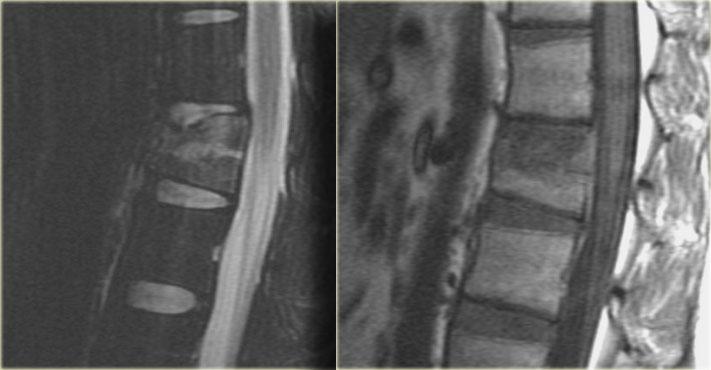

Tiếp tục với MR.

Các hình ảnh MRI cho thấy phù tủy xương ở thân đốt sống bị tổn thương, nhưng không có tổn thương phần mềm bổ sung.

Dựa trên việc MRI không cho thấy bất kỳ phát hiện bổ sung nào, bệnh nhân này được điều trị như trường hợp tổn thương một cột.

Tham khảo ý kiến phẫu thuật chỉnh hình khuyến nghị điều trị bảo tồn với nẹp TLSO.

Ngày nay có xu hướng điều trị bảo tồn các chấn thương cột sống ngực-thắt lưng này, ngay cả khi có tổn thương nhẹ ở cột giữa.

Vai trò của MRI trong những trường hợp này vẫn chưa được xác định rõ ràng.